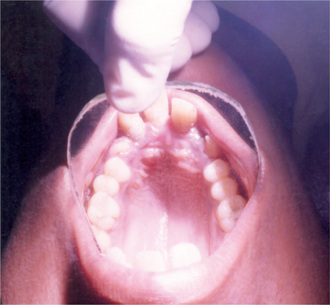

The jaws are involved in the same manner as the other bones in the body, and the oral manifestations have been reviewed by Kaslick and Brustein. However, a clear distinction has usually not been made as to the type of the disease present, benign or malignant. The medullary spaces of the jaws are remarkably reduced in both dominant and recessive osteopetrosis so that there is a marked predilection for the development of osteomyelitis should infection gain entrance to the bone. This is a complication of dental extraction which has been reported frequently and discussed by Dyson. Similar findings were noted by Bjorvatn and his associates in four children with the malignant form of the disease. They stressed the necessity of administering large doses of antibiotics to control the recurring infection, which even then did not prevent the progressive osseous destruction. Fracture of the jaw during tooth extraction, even when the extraction is performed without undue force, may also occur because of the fragility of the bone. It has been reported that the teeth are of defective quality, enamel hypoplasia, microscopic dentinal defects and arrested root development all having been described. However, this may not be true in the benign dominant form of the disease. It is also reported that the teeth are especially prone to dental caries. Since dental findings have been recorded in so few cases, this observation is difficult to evaluate. An additional rather constant finding is retardation of tooth eruption due to the sclerosis of bone.

Radiographic features are usually diagnostic. Because the disease is a heterogeneous group of disorders, the findings vary depending on the subtype. Patients usually have generalized osteosclerosis. Bones may be uniformly sclerotic, but alternating sclerotic and lucent bands may be noted near the ends of long bones (Fig. 17-6). The bones might appear club like or show an appearance of a bone within bone (endobone). The entire skull is thickened and dense, especially at the base. Sinuses are small and underpneumatized. Vertebrae are extremely radiodense. They may show alternating bands, known as the ‘rugger-jersey’ sign. Radiographs may show evidence of fractures or osteomyelitis. When the jaws are affected, the density of the bone may be such that the roots of the teeth are nearly invisible on the dental radiograph.